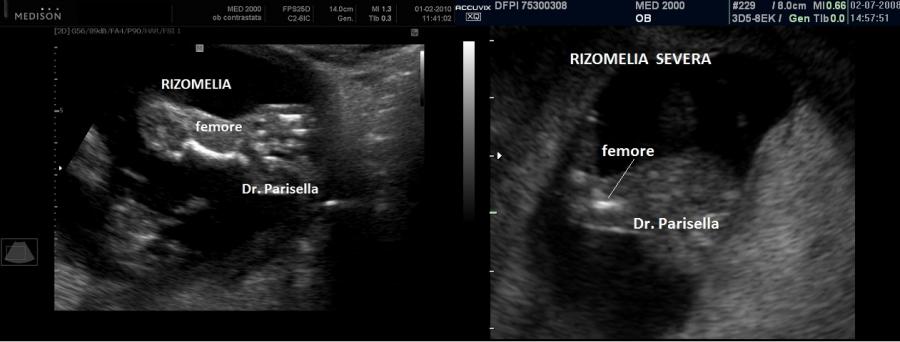

All'ecografia prenatale si riscontra ipoplasia toracica (torace stretto e coste corte), rizomelia lieve-moderata e frequentemente  displasia renale policistica.

Essendo la brevità degli arti frequentemente modesta la diagnosi prenatale è difficoltosa prima del terzo trimestre e comunque non può essere fatta prima della 24a settimana di gestazione.